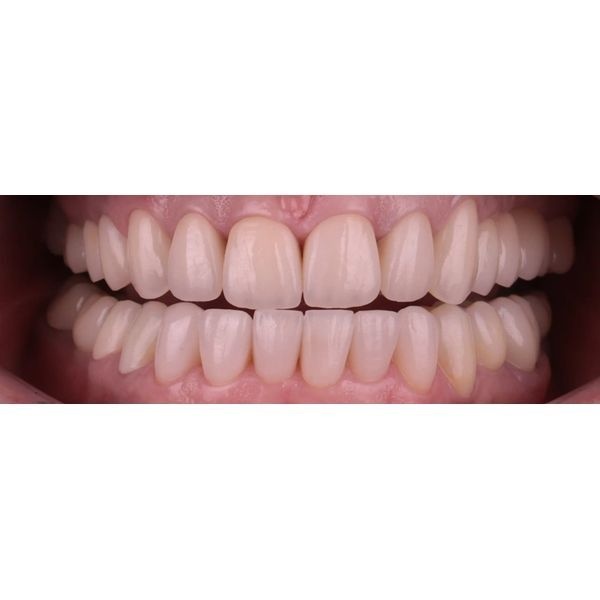

Когда суставные головки приняли нормальное положение, наступил этап изготовления постоянных конструкций. Из непротезированных зубов у пациентки остались только нижние 4 резца и 2 клыка.

Так как женщина хотела самые тонкие виниры с минимальной обработкой, ей установили ультраниры. Из-за поднятия прикуса и значительной стёртости зубов серьёзного препарирования не потребовалось, достаточно было под микроскопом сгладить острые грани и обозначить границы будущей конструкции для техника. Так удалось максимально сохранить твёрдые ткани зуба.

Кроме того, за счёт поднятия прикуса и изменения наклона верхних зубов нам удалось снизить нагрузку на центральные зубы, что минимизирует риск новых сколов в будущем.

В этом случае нам удалось добиться оптимального окклюзионного контакта. На динамических и статических пробах видно плотное, равномерное смыкание всех зубов. Это не только эстетически выигрышно, но и функционально: теперь жевание стало эффективнее, а нагрузка на суставы — физиологичнее.